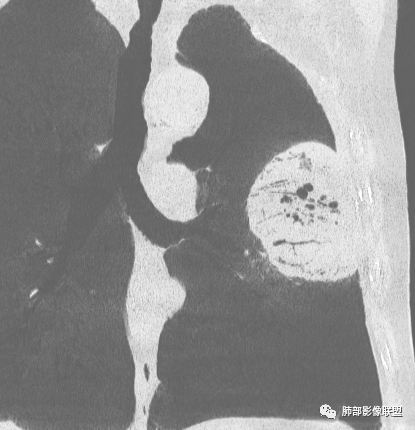

大肿块,边缘光滑,深分叶

近端支气管堵塞、推移为主

部分类似于脐凹征

内部支气管扩张

肺动脉推移为主,边缘部分进入

大肿块、表面光滑但深分叶,肺门侧支气管堵塞

回头看,内部支气管近端其实不连续,伴随肺动脉不存在

这两点就不符合

4)密度:肿块平扫为软组织密度,由于体积较大,内部常见大片状坏死,可出现不规则厚壁空洞或坏死内多发无壁小空洞,坏死多不均匀:坏死灶内可见如柳絮样的斑片样强化灶,坏死边缘与非坏死区分界不清本例坏死较明显,密度不均匀。

5)肿瘤强化方式:肺部恶性肿瘤强化程度与其血供丰富程度相关,血供丰富多强化明显,反之则较差。由于PSC 周边实性部分富血供及内部黏液变性、坏死,增强后肿块多数呈轻-中度边缘环形强化或不均匀小斑片状强化。国外学者对照病理发现肿瘤细胞或胶原组织增强扫描时强化,无强化的低密度区代表了黏液样变性区和出血坏死区。